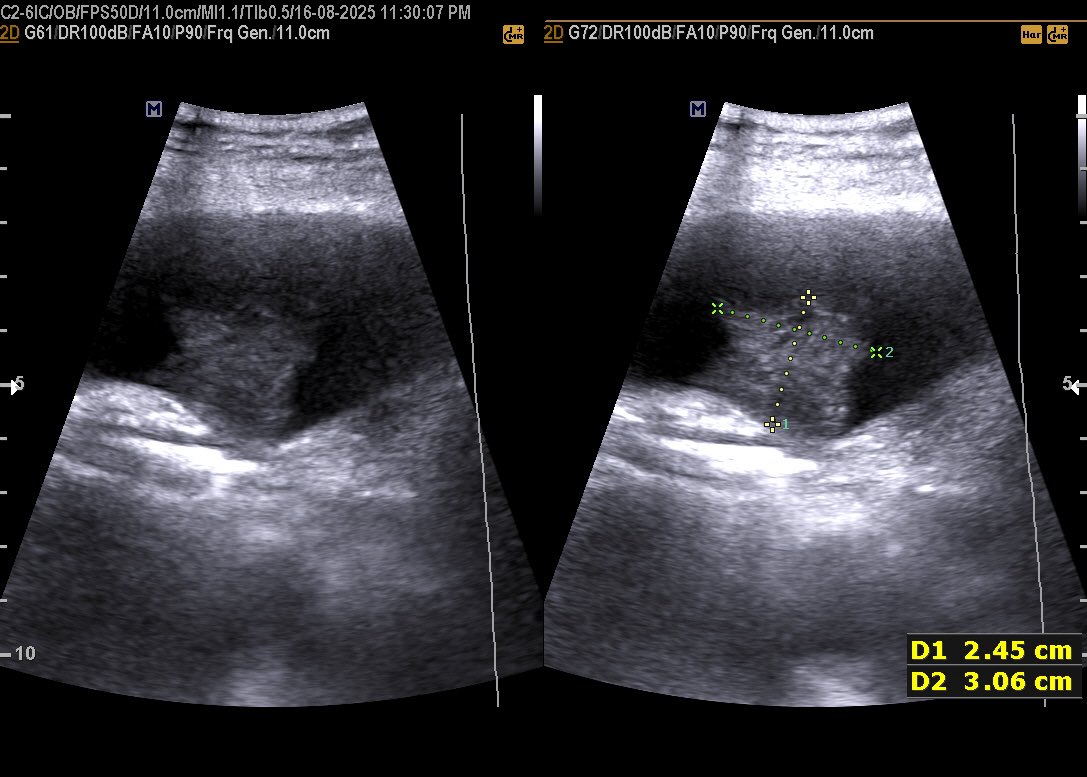

𝗖𝗘𝗥𝗩𝗜𝗖𝗔𝗟 𝗟𝗘𝗡𝗚𝗧𝗛 𝗜𝗡 𝗨𝗟𝗧𝗥𝗔𝗦𝗢𝗨𝗡𝗗 Normal Cervical Length : ≥25 mm Risk starts : <25 mm Serious risk : <15 mm #EchoTech

𝗖𝗘𝗥𝗩𝗜𝗖𝗔𝗟 𝗟𝗘𝗡𝗚𝗧𝗛 𝗜𝗡 𝗨𝗟𝗧𝗥𝗔𝗦𝗢𝗨𝗡𝗗 Normal Cervical Length : ≥25 mm Risk starts : <25 mm Serious risk : <15 mm #EchoTech

𝗖𝗘𝗥𝗩𝗜𝗖𝗔𝗟 𝗟𝗘𝗡𝗚𝗧𝗛 𝗜𝗡 𝗨𝗟𝗧𝗥𝗔𝗦𝗢𝗨𝗡𝗗 Normal Cervical Length : ≥25 mm Risk starts : <25 mm Serious risk : <15 mm #EchoTech